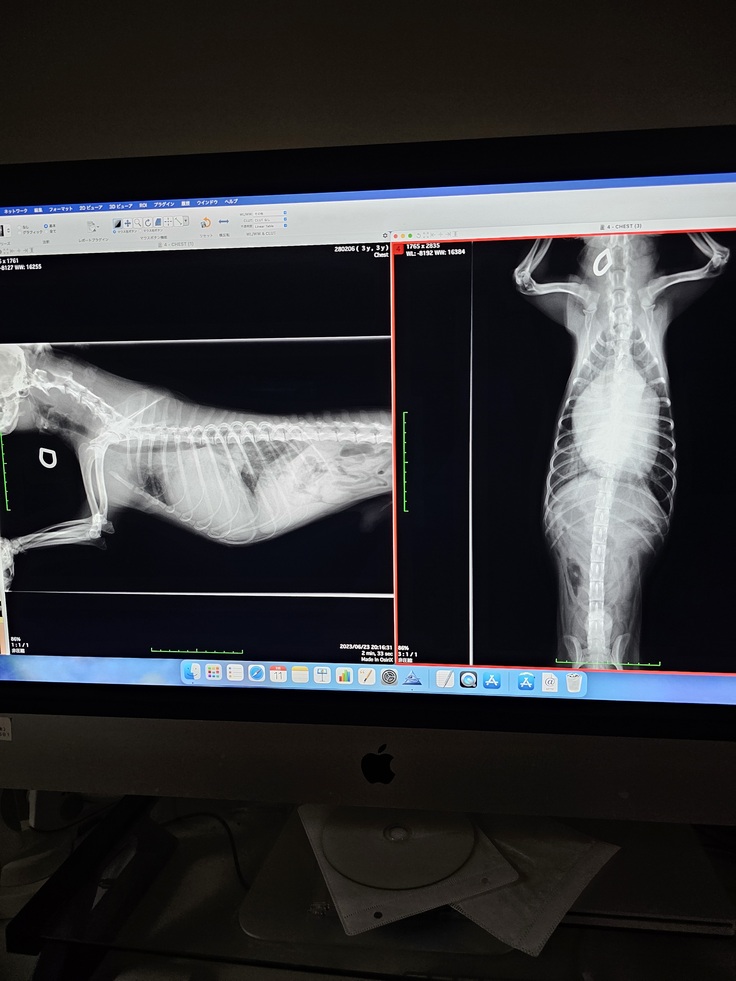

7月18日病院に行きました。

右側が初診の時に撮ったレントゲン。

左側は今日撮ったレントゲンです。

肺に溜まっていたお水も抜け、心臓が少し縮んでいます。

血液検査でも腎臓の数値は正常範囲内。

脱水は起きてます。

そのお陰で心臓が前回より縮んでくれました。

お薬は前回と同じになりました。

今日も利尿剤の注射を打って貰ってます。